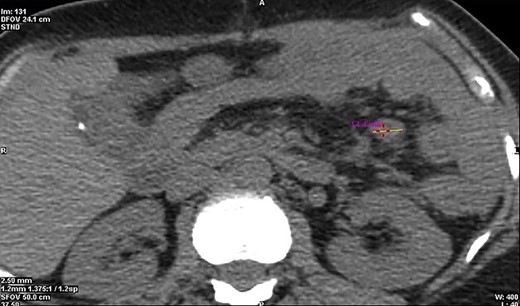

SPECT/CT Octreotide imaging. (A) A CT cross-section view indicating the location of the malignant lymph node. (B) A SPECT cross-section of the same plane indicating high uptake over the Region of Interest. (C) A combined view of SPECT/CT with superimposed images demonstrating hotspot over the malignant lymph node. (D) Octreotide SPECT coronal view showing the position of the malignant lymph node.

Initial basic laboratory investigations on presentation are mentioned above; however given the complexity of this case, further investigation was required. An octreotide single-photon emission computed tomography (SPECT/CT) imaging was performed in hope to identify any additional active tumour cells (Fig. 1). An avid ~15 mm node was noted in the proximal mesenteric jejunum (Fig. 2), as seen intra-operatively, with no additional pancreatic, small bowel or colonic uptake. Other specialized laboratory investigations included chromogranin A&B, which were within normal values of 20 and 88 pmol/L, respectively. 24-h urine 5-HIAA test was also normal of 14 μmol/24 h. The overall image and appearance closely points to a well-differentiated grade 2 neuro-endocrine carcinoma.

CT cross-section illustrating a diameter of 14.4 mm of the malignant neuroendocrine tumour.